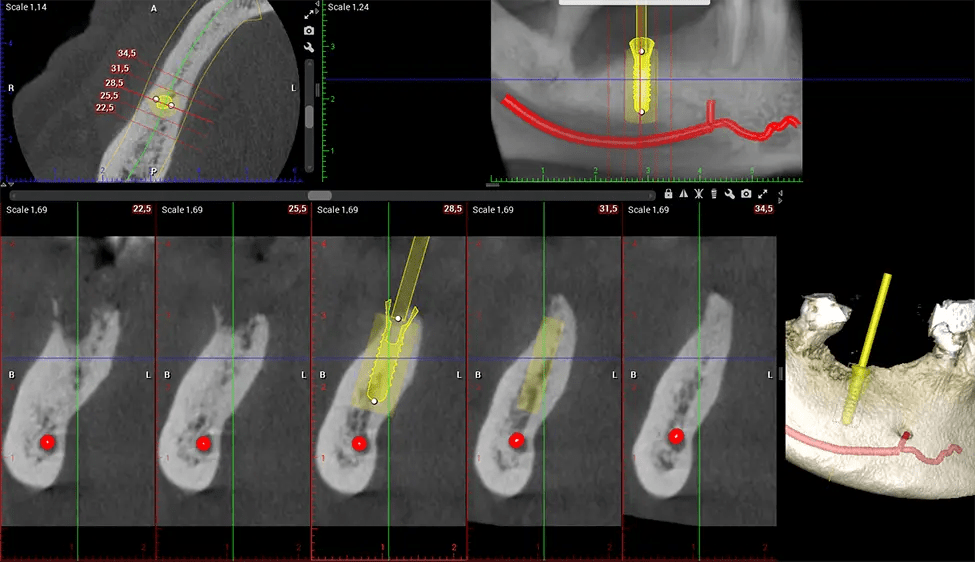

When paired with extractions, dental implant placement, or bone grafting, CBCT technology can provide you with a quicker and much more comfortable experience. This is because the 3D image provides a more detailed picture of your entire oral cavity, allowing your dentist to walk you through each step of the process before it occurs. This often helps patients feel more prepared and comfortable overall, especially if they have had a traumatic experience with past dental treatments.

Oral and Maxillofacial Surgeon Complex oral surgeries, orthognathic (jaw) surgery, and removal of impacted teeth. Offers precise, three-dimensional visualization of the skull, jaw, and craniocervical junction to enhance diagnostic accuracy and minimize surgical risks.

Orthodontist Assessing facial asymmetry, planning orthognathic surgery, and managing cleft lip and palate and sleep apnea. Provides a comprehensive view of the craniofacial complex to better plan treatments and evaluate outcomes.